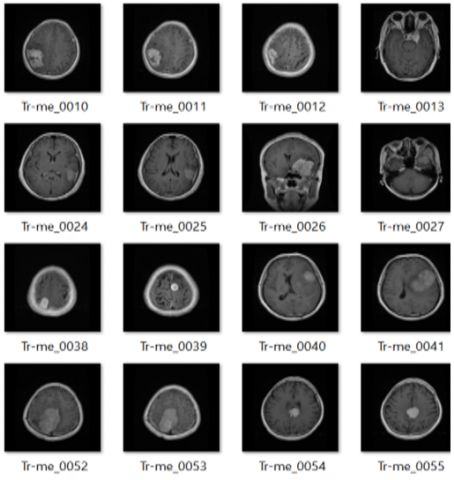

The dataset used for this work was obtained from the Kaggle websitehttps://www.kaggle.com/datasets/masoudnickparvar/brain-tumor-mri-dataset). The images are provided in .jpg format to standardize input values; all images are resized to 224 × 224 pixels, and pixel intensities are normalized to the range [0, 1] by dividing by 255. The dataset included 490 Glioma Tumors, 364 Meningioma Tumors, 617 Pituitary Tumors, and 423 No-tumour images. The dataset is divided into a 70% training set and a 30% test set. The test set contained 147 Glioma Tumors, 109 Meningioma Tumors, 185 Pituitary Tumors, and 127 No-tumour images. The visualization of data set images is shown in Figure 4.

Figure 4. Dataset visualization